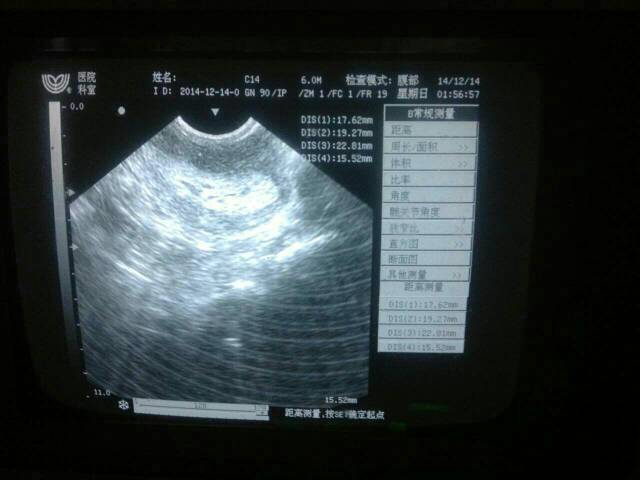

早孕试纸自测率为75%,5分钟内观察有效,有是可出现假阴性或假阳性,在月经延迟10天后检查结果较为准确。月经周期一般延迟一周左右仍属于正常范围。你的情况,如果担心怀孕,可严密观察,如果月经延迟一周以上,则到正规医院妇科进行血HCG、B超等相关检查,确诊是否怀孕